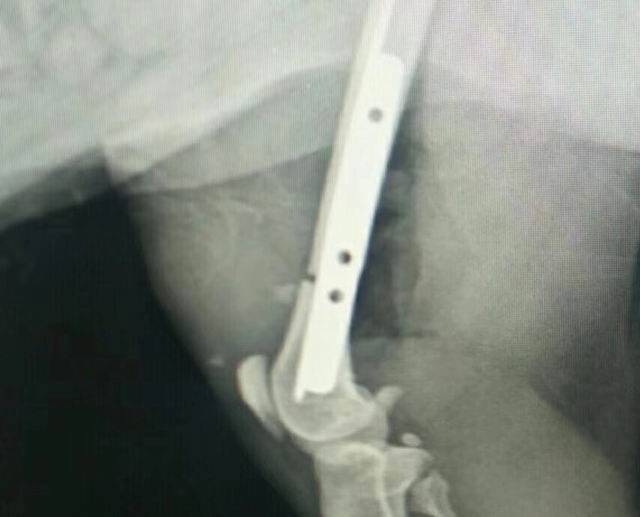

一例貓咪骨折/內(nèi)固定術

藍白,2歲,外固定失敗轉于我院,實施骨折內(nèi)固定,術前體檢+進口麻藥+手術順利(ok),住院護理中……急主人所急,想主人所想,致力于寵物健康,洛陽狗博仕寵物醫(yī)院